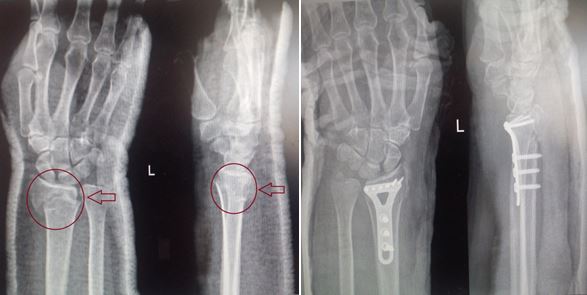

Переломы костей предплечья

Предплечье формирует 2 кости: локтевая и лучевая. Предплечье имеет сложную анатомию. В этой области расположился большой спектр анатомических образований (сухожилий, мышц, нервов), способствующих нормальному функционированию всей верхней конечности и кисти. Наиболее часто встречающиеся травмы в области предплечья:

- переломы дистального метаэпифиза лучевой кости;

- переломы лучевой кости в «типичном месте»;

- диафизарные переломы.

Основным методом выбора лечения таких пациентов является внутренний остеосинтез пластинами. При переломах обеих костей предплечья принято выполнять остеосинтез двумя накостными пластинами, что позволяет снизить травмирование мягких тканей. Операцию проводят через два отдельных доступа.